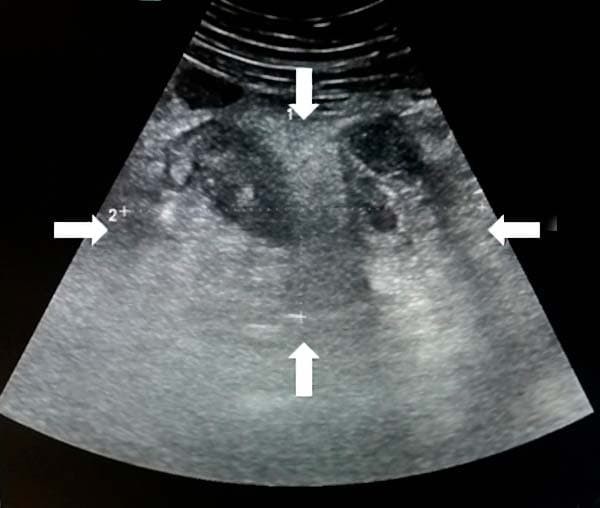

Из протокола УЗИ: «В правой подвздошной области визуализируется инфильтрат, определяется свободная жидкость межпетельно» (см. рис. 17).

Рисунок 17. УЗ-визуализация инфильтрата.

Из протокола операции: «Во всех отделах брюшной полости гной. Петли тонкой кишки раздуты, гиперемированы, отечны. В правой подвздошной ямке инфильтрат, состоящий из купола слепой кишки, червеобразного отростка, петли тонкой кишки, париетальной брюшины» (см. рис. 18).